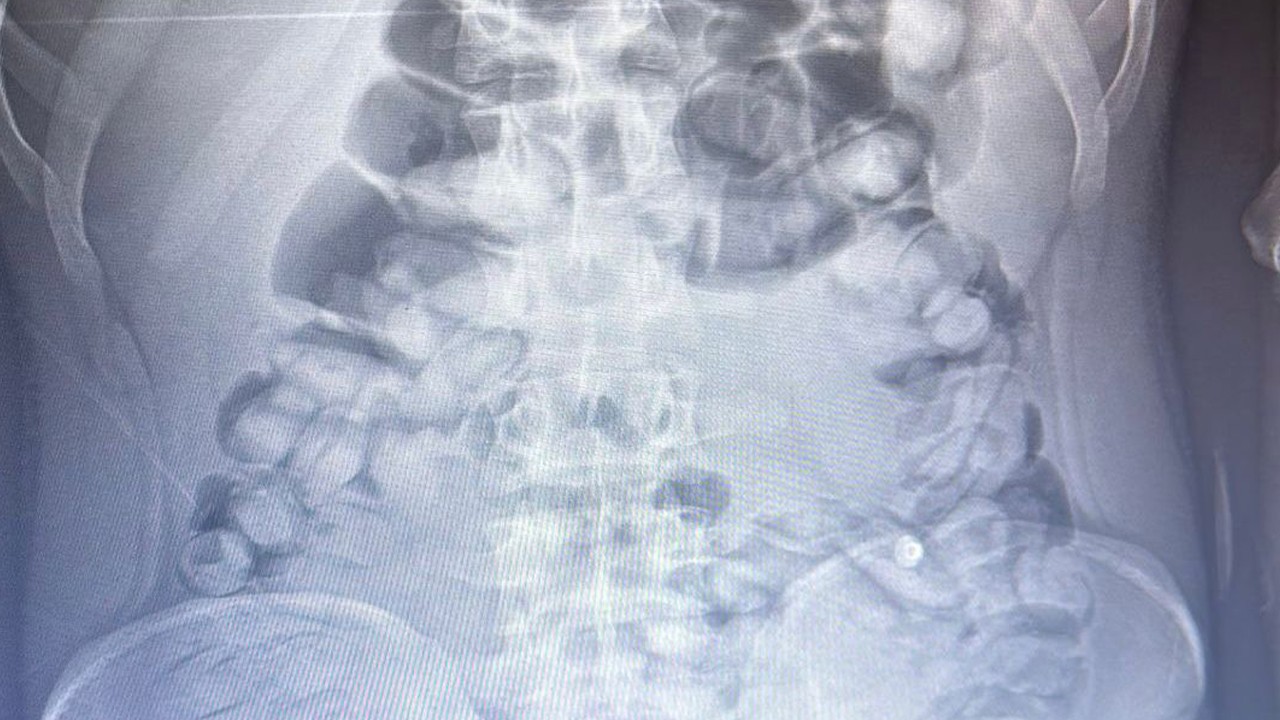

Erzurum'da, yolcu otobüsünde şüphe üzerine hastanede röntgeni çekilen yolcunun midesinde Afyon sakızı, tespit edildi. Yolcu, midesindeki 1 kilo 134 gram Afyon sakızını doğal yollarla çıkardı.

İl Emniyet Müdürlüğü Narkotik Suçlarla Mücadele Şube Müdürlüğü ekipleri, bir yolcu otobüsünde yaptığı denetimde, durumundan şüphelendiği yolcuyu hastaneye götürdü. Burada röntgeni çekilen yolcunun midesinde uyuşturucu tespit edildi. İlaç verilen yolcu, 1 kilo 134 gram Afyon sakızını doğal yollarla çıkardı.